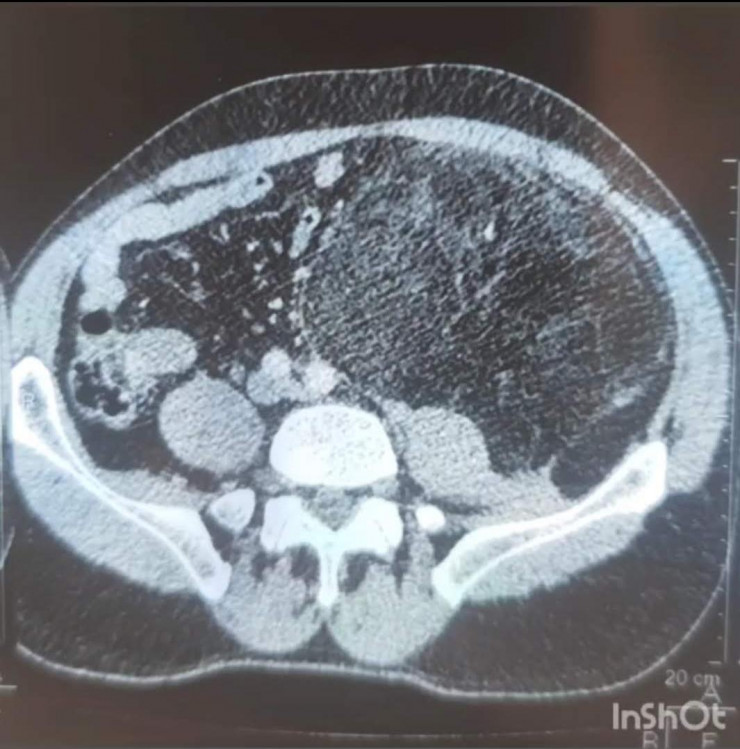

На КТ было обнаружено объемное образование. После тщательных анализов и обследований консилиум решил делать операцию по удалению образования.

Пациенту был выставлен диагноз – образование забрюшинного пространства с переходом в пахово-бедренную область слева.

"Сложность операции заключалась в самом расположении образования. Оно сдвинуло все органы брюшной полости в одну сторону, разместившись на всей левой половине. Границы образования находились очень близко к аорте, образование практически лежало на аорте, прилегая к левой почке и мочеточнику, а внизу образование ушло через паховую область, проходя совсем рядом с бедренной артерией в верхнюю треть бедра. Сложность доступа заключалась в том, что нужно было сделать дополнительный разрез в паховой области. Чтобы извлечь образование, пришлось в три руки очень осторожно отделять образование от органов, к которым оно буквально приросло. Образование удалось извлечь, не нарушив целостности, что очень важно", - объяснил заведующий операционным блоком ГБСНП Нуркен Желдибаев.

На момент операции размер образования был 25-30 сантиметров, а вес образования составил 2,240 килограмма.